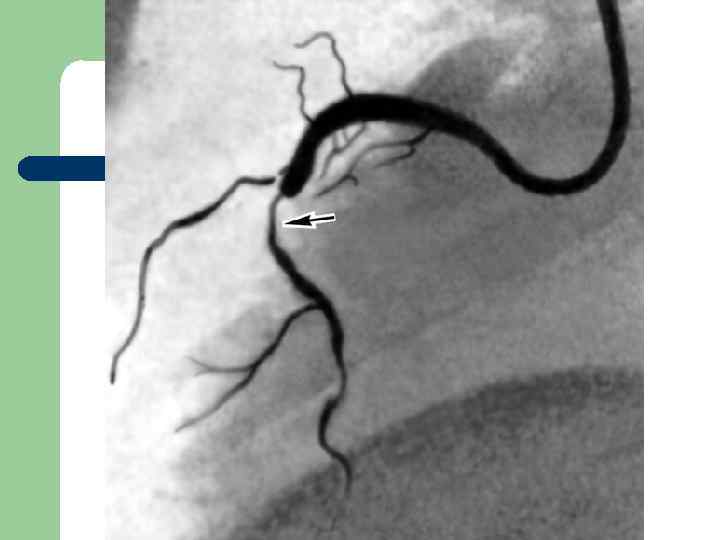

Коронароангиография «золотой стандарт» диагностики стенозирующих поражений коронарных артерий и ключевой метод для принятия решения о необходимости и способе реваскуляризации. Но… помнить концепцию Glagov!

Показания к КАГ l l l l l Стенокардия, сохраняющаяся на фоне адекватной терапии и после ЧТКА. Стенокардия Принцметала. Нестабильная стенокардия при отсутствии эффекта от адекватной медикаментозной терапии. Резко положительные нагрузочные пробы. Состояние после реанимации по поводу ВАС. Аортальный стеноз, ГКМП, другие заболевания, где ангинозная боль может быть обусловлена коронарным атеросклерозом. Предстоящая операция по поводу клапанных пороков в возрасте риска ИБС. Постинфарктная стенокардия. Осложнения ОИМ: разрыв МЖП, митральная регургитация, осложнённая аневризма ЛЖ. Невозможность устранить сомнения в диагнозе ИБС другими способами.